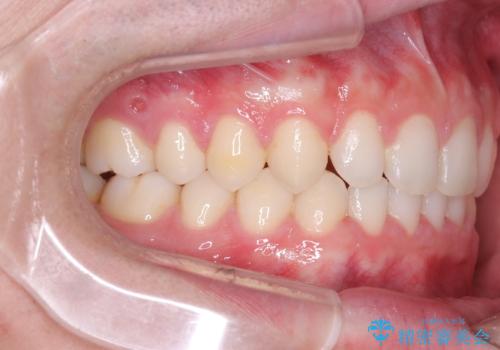

- 主訴:上の歯列の空隙を閉じたい

上顎前歯部に空隙が目立ちました。ワイヤー矯正、インビザライン(マウスピース矯正)どちらの方法でも適用症例と説明し、ワイヤー矯正治療(審美装置)を希望されました。

上顎歯列の空隙を閉じるのと一緒に、ディープバイト気味の被蓋も下顎前歯の圧下を行い改善しました。